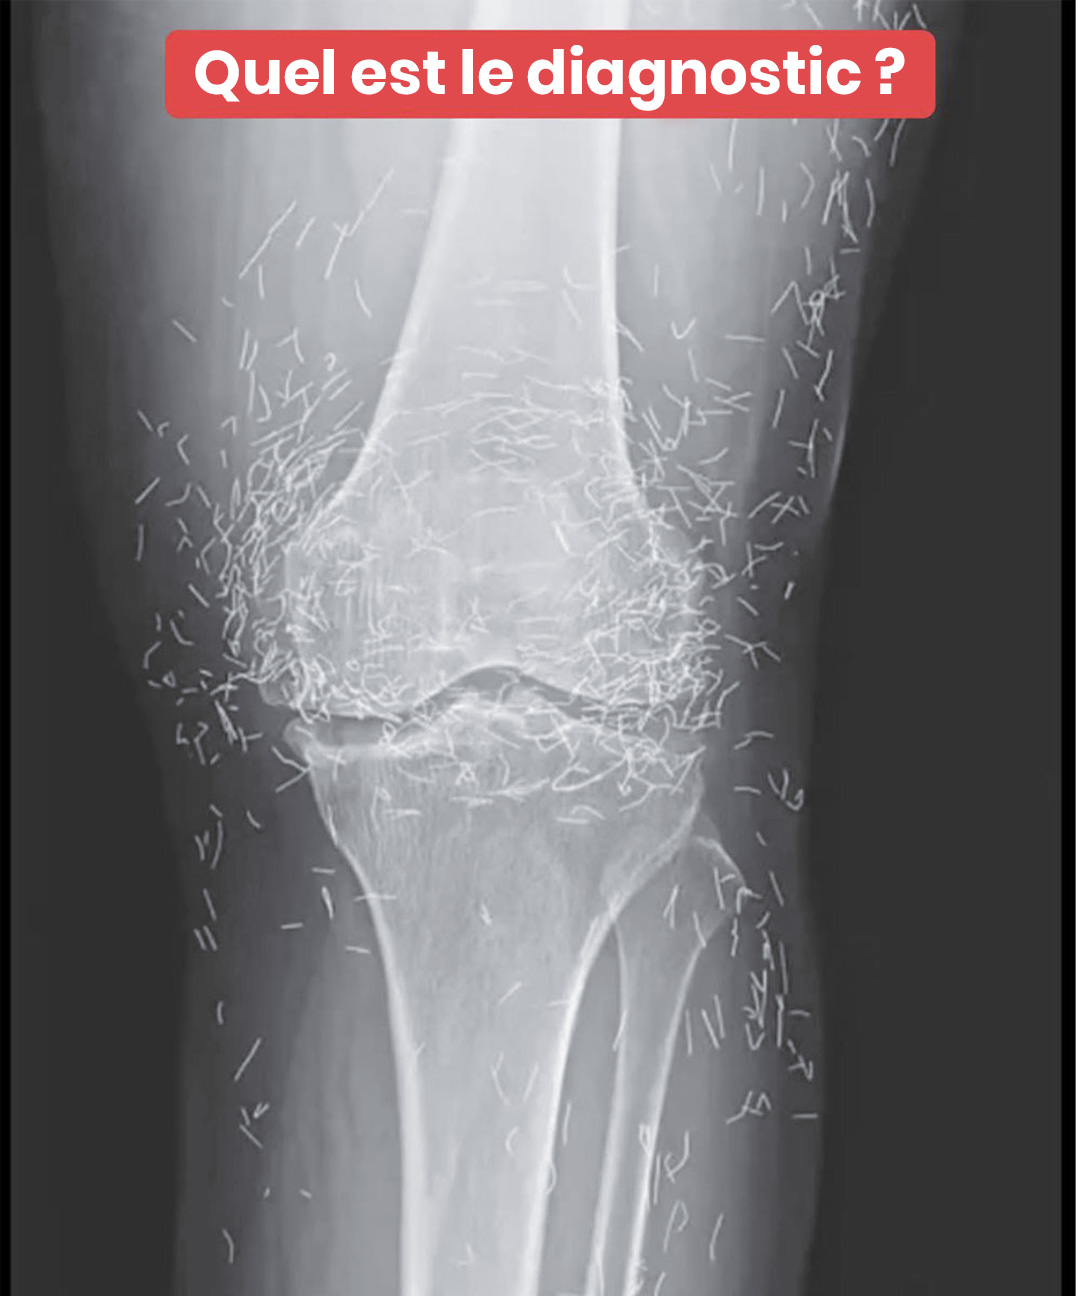

C’est lors d’un examen radiologique de routine que les médecins ont découvert, surpris, des centaines de petites aiguilles brillantes disséminées autour de ses genoux. Une véritable curiosité médicale qui a suscité à la fois étonnement et prudence. Car si l’or est un métal inerte et bien toléré, la présence prolongée d’objets étrangers dans le corps n’est jamais anodine.

D’après des spécialistes en imagerie médicale, ces aiguilles peuvent masquer certaines zones du corps sur une radiographie, rendant plus difficile le diagnostic d’autres problèmes. Et surtout, elles compliquent sérieusement la réalisation d’un examen IRM : le risque que les aiguilles bougent sous l’effet du champ magnétique est réel, ce qui pourrait endommager des tissus sensibles.